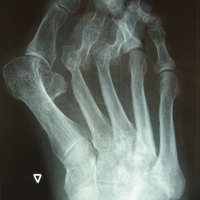

• Κότσια - Εξαρθρήματα μεταταρσίων